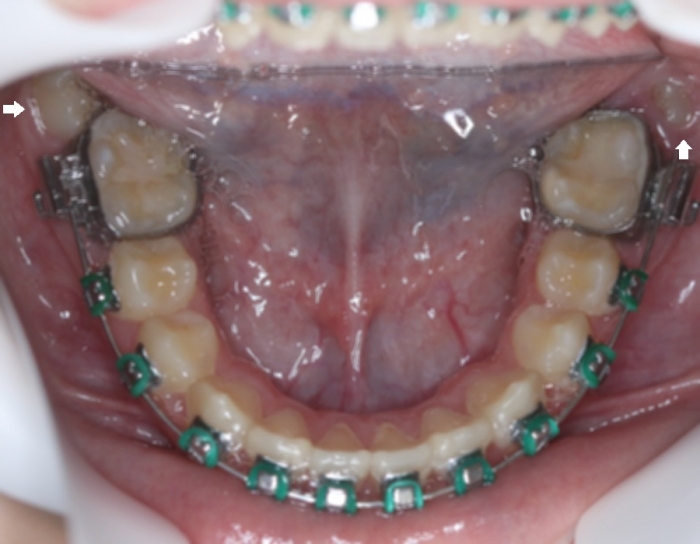

Oclusal inferior com segundos molares em posição inadequada - Clínica Cliniface

Oclusal inferior com segundos molares em posição inadequada